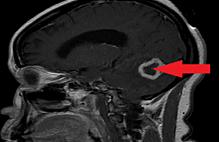

The patient was admitted for fungal osteomyelitis with Candida glabrata and treatment with intravenous micafungin was begun. After six months of treatment, his infection resolved and he was discharged. At two-year follow-up, his back pain has fully resolved (VAS Analog Scale 1/10) and an MRI revealed resolution of the infection (Figure 3).